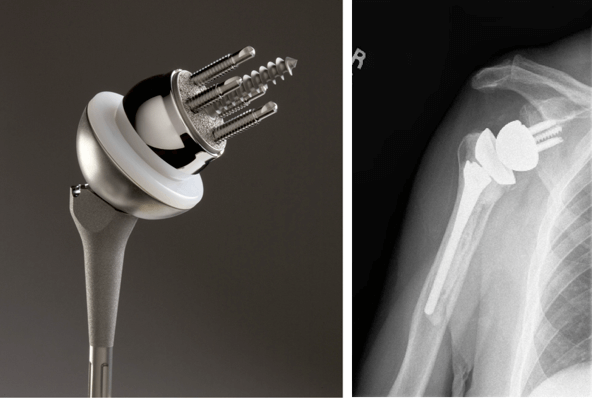

В Новосибирском НИИТО накоплен опыт клинического наблюдения патологии локтевого сустава в течение более чем 30 лет. В работе использованы эндопротезы локтевого сустава фирмы ЭСИ (авторская разработка В.М. Прохоренко), а также эндопротез фирмы Zimmer (рис. 1). Во всех случаях использовался связанный тип имплантатов с цементной интрамедуллярной фиксацией.

Рис. 1. Виды эндопротезов локтевого сустава, применяемые в Новосибирском НИИТО:

ЭСИ (А); эндопротез фирмы Zimmer (Б)